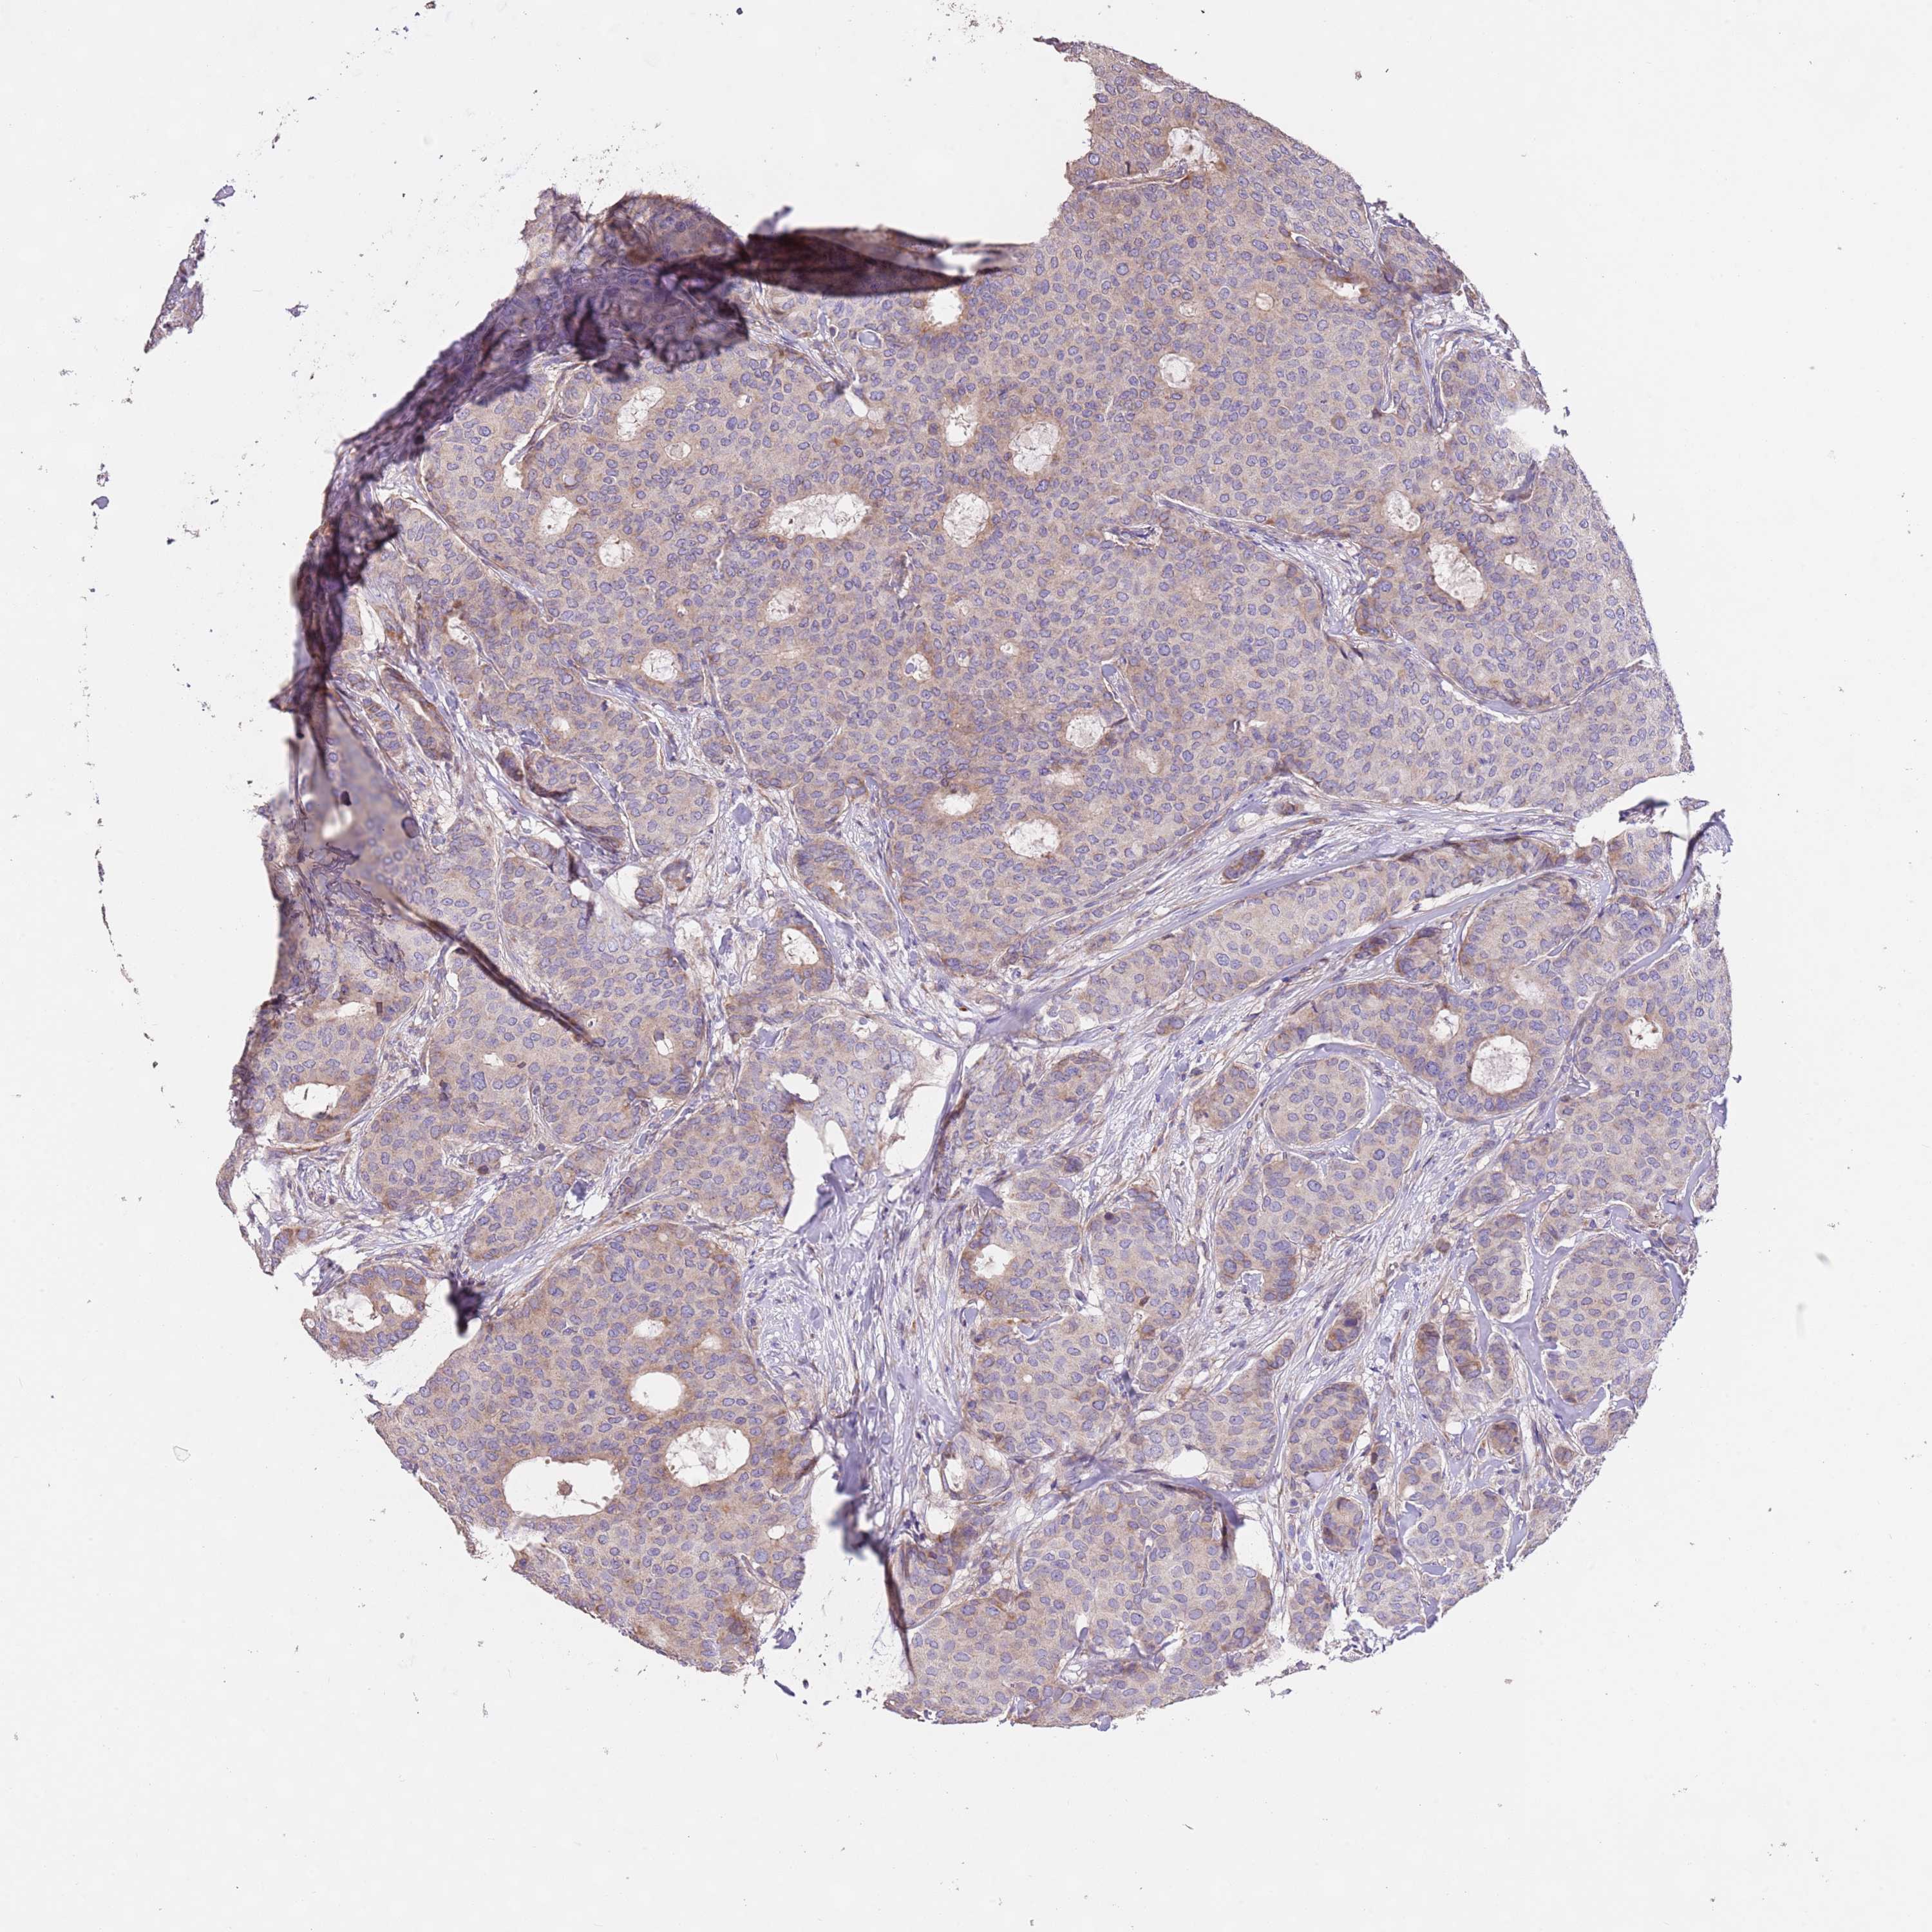

CANCER BREAST CANCER Show tissue menu

BRCA TCGA BRCA VALIDATION PROTEIN EXPRESSION